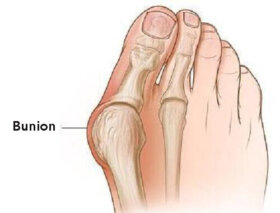

건막류는 엄지발가락의 관절이 커져 뼈나 조직이 이탈되면서 발생하는 질환이다. 오늘은 건막류가 생기는 이유를 보다 더 자세하게 알아보자.